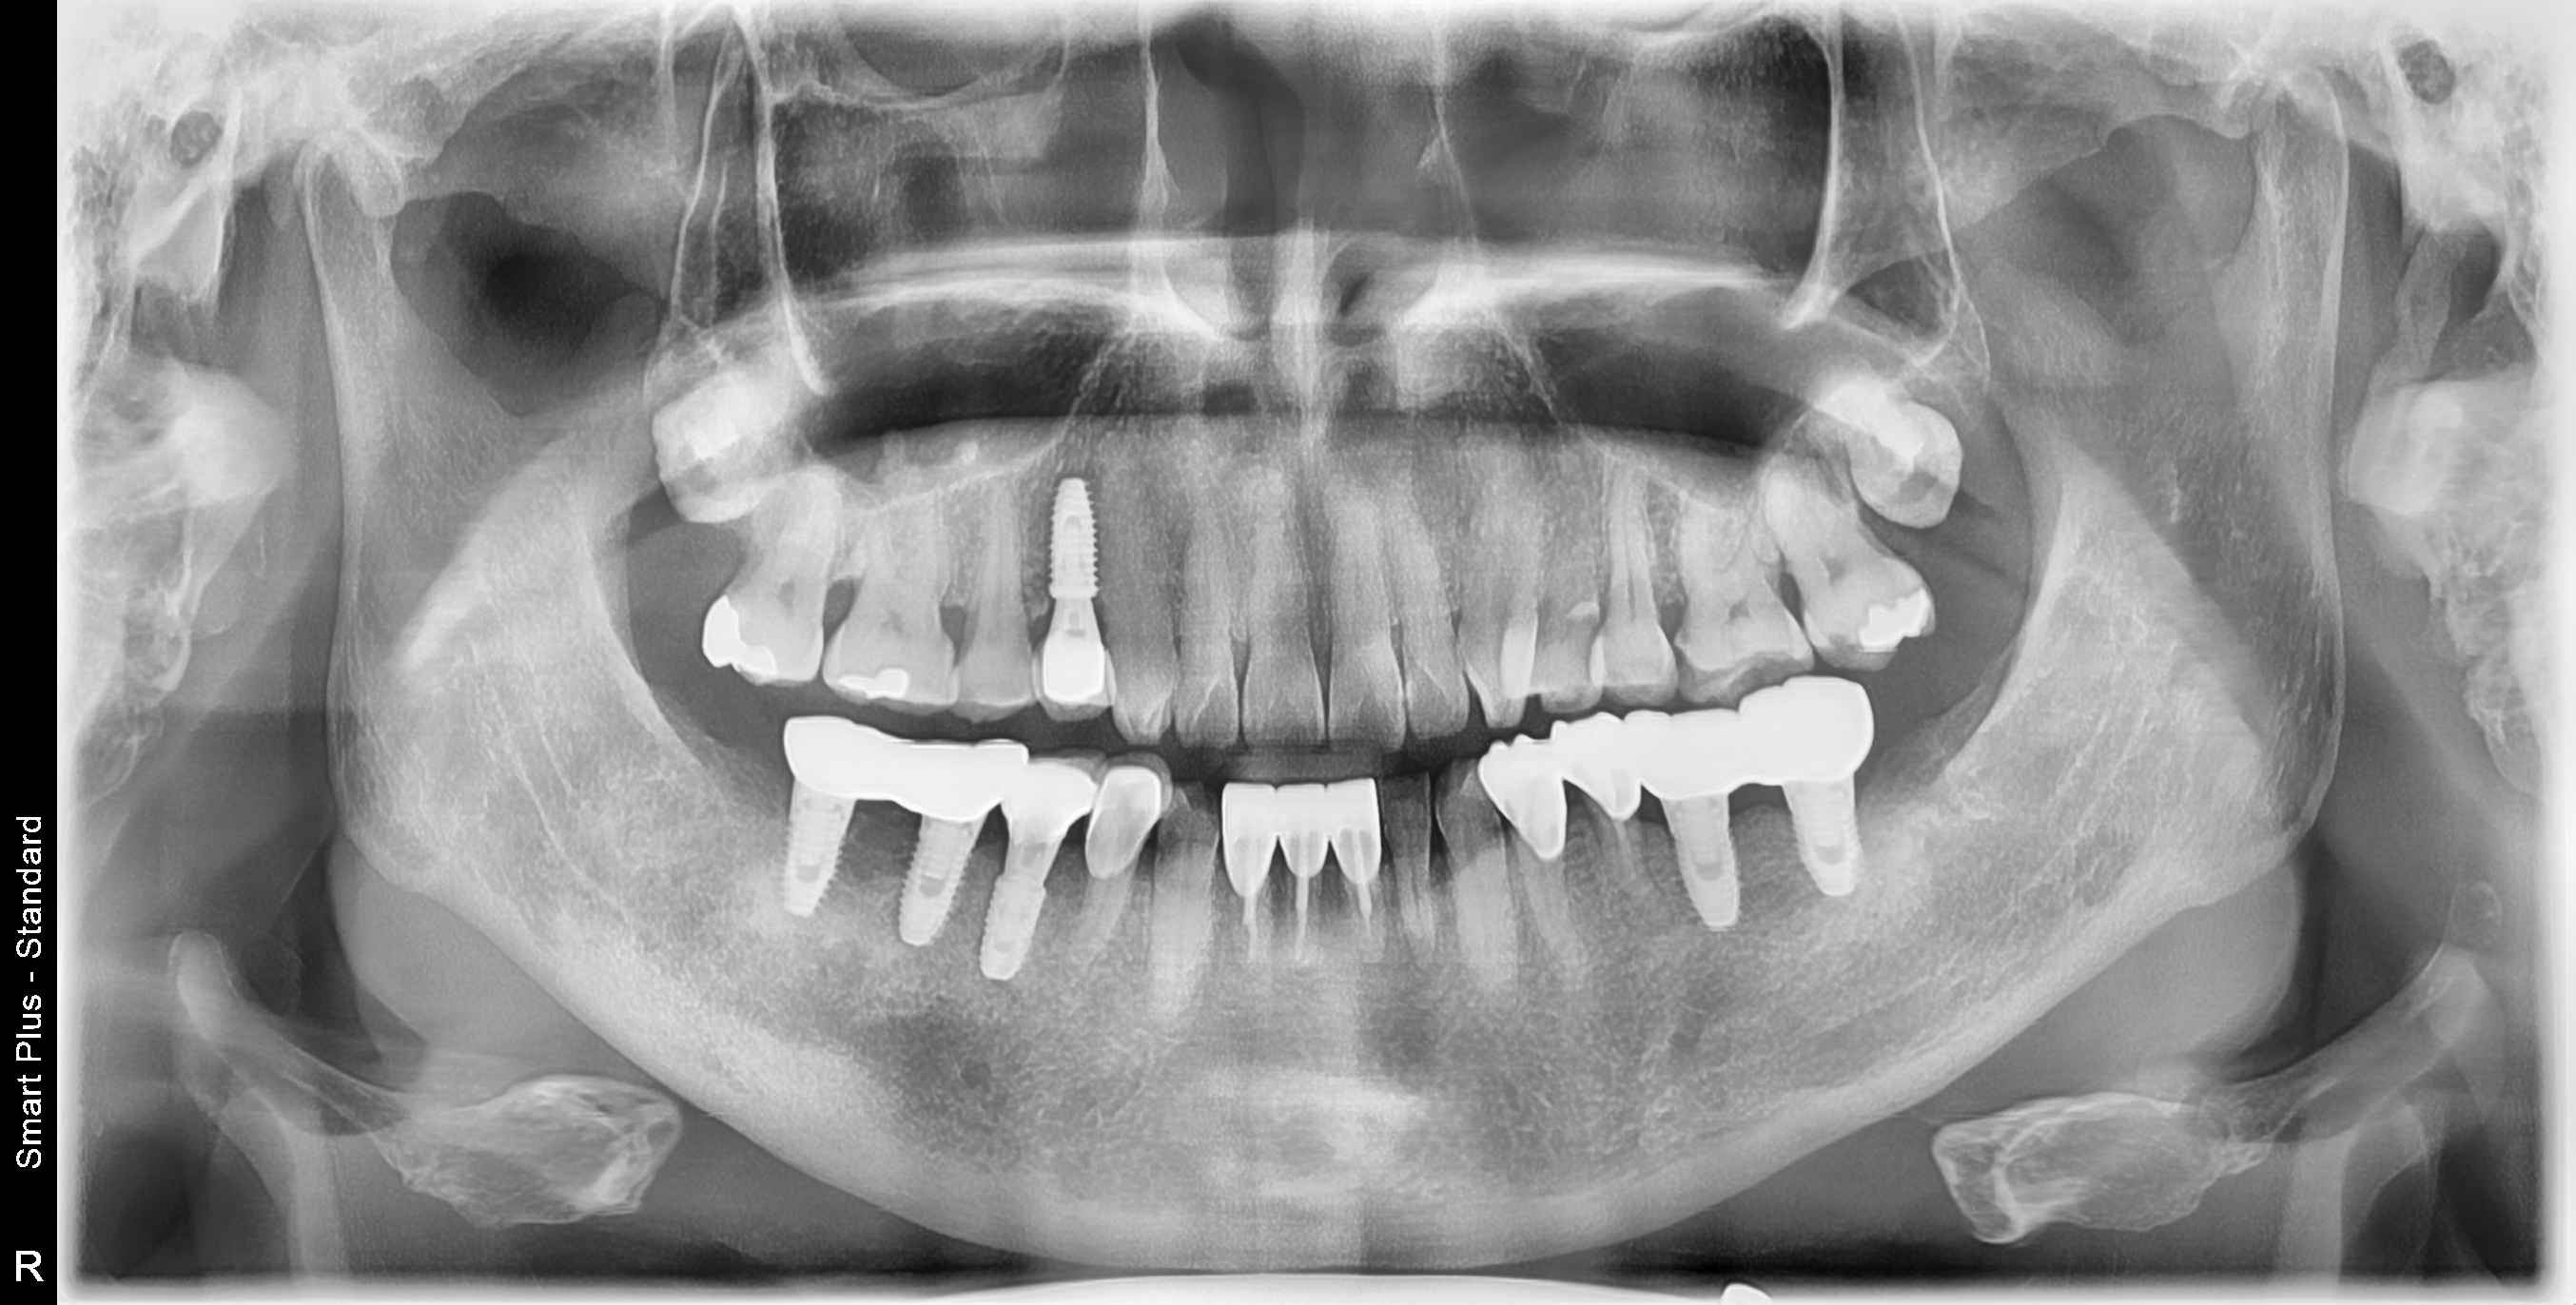

[임플란트] 제목 : 틀니 사용중, 임플란트로 교체하기

하악틀니 사용 중 불편감으로 임플란트로 교체한 예